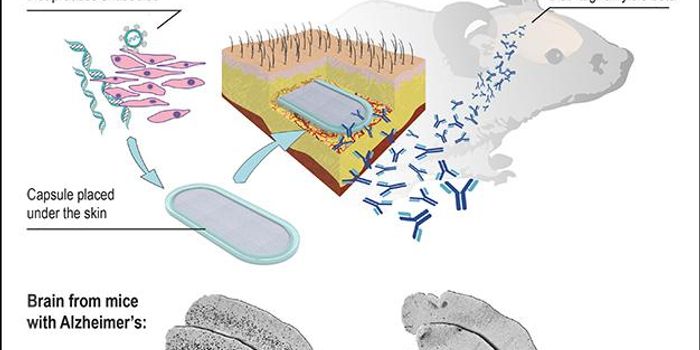

MAR 18, 2016Health & MedicineScientists have developed a brain implant that can turn the patient’s immune system against Alzheimer’s dise ...